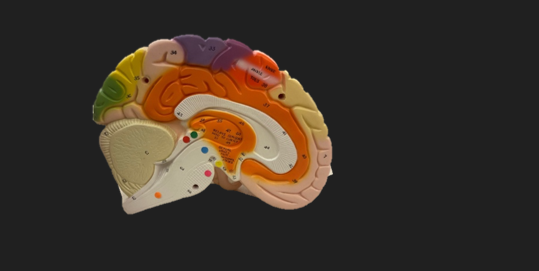

frontal lobe

blue dot

longitudinal fissure

dark green dot

precentral gyrus

pink dot

postcentral gyrus

yellow dot

central sulcus

white dot

parietal lobe

light green dot

Broca’s Area

red dot

Wernicke’s Area

orange dot

occipital lobe

blue dot

parieto-occipital sulcus

blue dot

olfactory tract

red dot

corpora quadrigemina

dark green dot

cerebral aqueduct

blue dot

cerebral penduncles

pink dot

pons

orange dot

medulla oblongata

yellow dot

mammillary body

red dot

corpus callosum

dark green dot

pineal gland

yellow dot

epithalamus

blue dot

thalamus

orange dot

optic chiasm

pink dot

infundibulum

purple dot

cingulate gyrus

yellow dot

pituitary gland

dark green dot

pyramids

red dot

olives

blue dot

optic tract

purple dot

midbrain

green dot

folia

orange dot

arbor vitae

yellow dot

fourth ventricle

red dot

vermis

blue dot

hypothalamus

pink dot

cerebral hemispheres

yellow dot

lateral sulcus

red dot

lateral ventricles

blue dot

hippocampal gyrus

green dot

olfactory tract